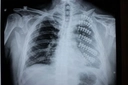

Kolda doku zedelenmesi yaşadıktan sonra ne yapmalıyım? Morarma ve şişlik oluştu, bu normal mi? Ayrıca, bu tür bir zedelenmenin iyileşme süresi ne kadar sürer? Spor yaparken bu durumdan nasıl korunabilirim? Tecrübelerinizle yardımcı olursanız sevinirim.

Kolda Doku Zedelenmesi Sonrası Yapılması Gerekenler

Eğer kolda doku zedelenmesi yaşadıysanız, öncelikle bölgeyi dinlendirmelisiniz. Morarma ve şişlik normal bir tepki olabilir, ancak bu belirtiler şiddetliyse bir sağlık profesyoneline danışmanızda fayda var.

Morarma ve Şişlik Normal Mi?

Evet, zedelenme sonrası morarma ve şişlik sıkça görülen durumlardır. Bunun nedeni, kan damarlarının hasar görmesi ve sıvı birikmesidir. Ancak, bu belirtiler uzun sürerse veya ağrı artarsa, bir doktora görünmelisiniz.

İyileşme Süresi

İyileşme süresi, zedelenmenin ciddiyetine bağlı olarak değişir. Hafif bir zedelenme genellikle birkaç günde iyileşirken, daha ciddi yaralanmalar birkaç hafta alabilir.